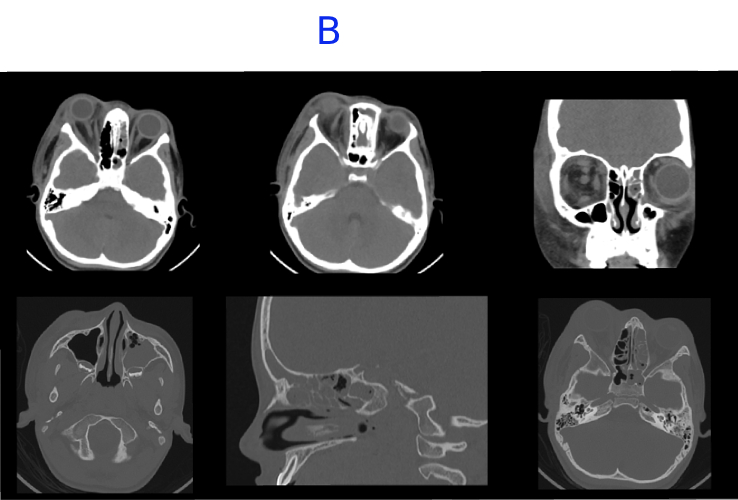

B. FINDINGS – CT PNS WITHOUT IV CONTRAST - DAY 2

B. Mild interval increase in hypodense collection along medial wall of right orbit. There is interval appearance of edema and fat stranding in periorbital soft tissue and preseptal space in the left orbit. Near complete mucosal opacification with bubbly secretions of left maxillary, ethmoid, frontal and sphenoid sinus with bubbly secretions. Mild mucosal thickening in the right ethmoid and sphenoid sinus.Opacification in left middle ear cavity and left mastoid air cells.